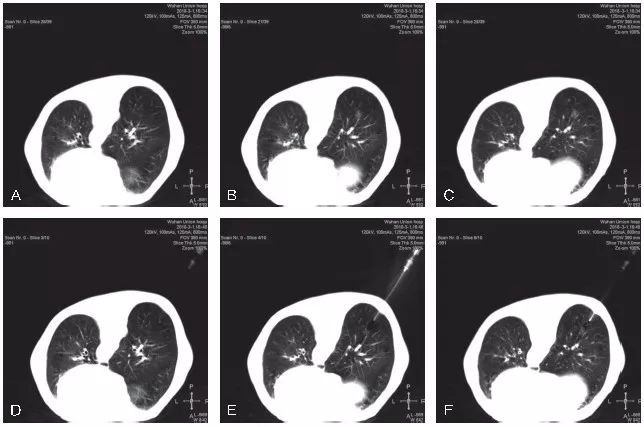

图5-4 展示了1例mGGO的CT 引导下经皮穿刺活检

A~C. 显示患者右肺下叶后基底段mGGO,实性成分处可见胸膜牵拉,选取俯卧位进行穿刺活检;D~F. 显示穿刺活检的实时CT影像,可见同轴穿刺针前端位于mGGO的实性成分处;G~L. 显示活检完成后,拔除同轴穿刺针,再次进行CT扫描,未见明显气胸及肺内出血征象。病理结果示:(右肺)肺泡腔扩张伴肺泡间隔炎性细胞浸润及组织细胞聚集,局灶浆细胞聚集,未见明确肿瘤性病变,请结合临床。